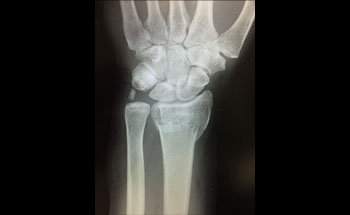

This clinical practice guideline addresses the treatment of distal radius fractures in adults(> 18 years). It is limited to the treatment of acute distal radius fractures and does not address distal radius malunion.